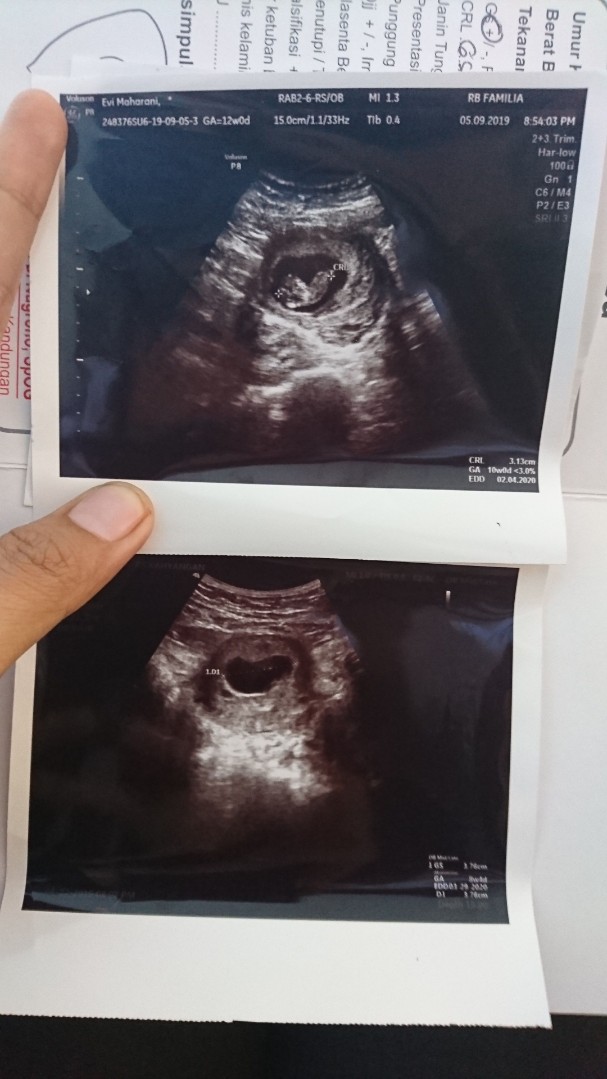

Kehamilan aku yg skrg bund. Usg yg bawah 2mggu yg lalu uk 8w msih kantongnya aja blm ada janinnya. 2mggu kmudian aku usg lg alhamdulillah udah ada janinnya, yg atas foto baru kmrn ini usg udh kliatan janin sma dtak jantung janinnya usia 10w. Oiya bund aku jg sama kok gak ngalami mual muntah sma skali dari awal kehamilan. Positif thinking aja bund